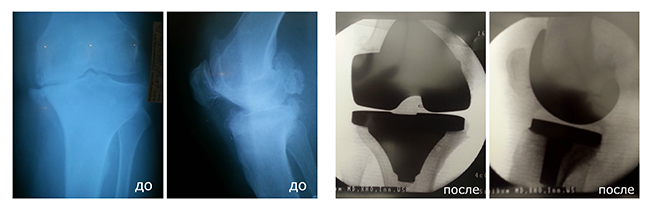

Эндопротезирование коленного сустава

Лечению такой сустав уже не подлежит, поскольку сам хрящ уже разрушен, и единственным способом вернуть человека к нормальной жизни является операция – эндопротезирование коленного сустава. Только благодаря ей человек сможет снова почувствовать радость от движения!

Существует два вида эндопротезирования коленного сустава: тотальное и частичное. Каждое из них применяется в зависимости от случая пациента.